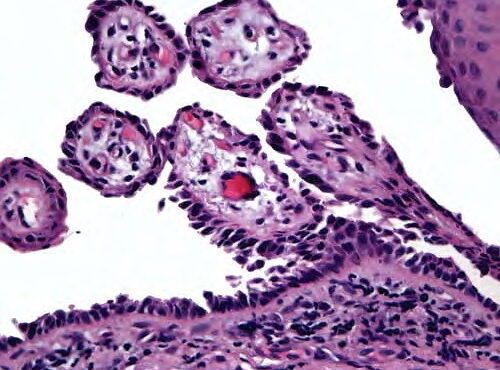

Papillary eccrine adenoma = الغدوم الناتح الحطاطي

Papillary eccrine adenoma = الغدوم الناتح الحطاطي OLYMPUS DIGITAL CAMERA OLYMPUS DIGITAL CAMERA